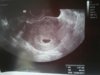

No i trochę za wcześnie... Ale przed badaniem mi powiedział, że skoro owulację miałam 17 września to będzie jeszcze sam pęcherzyk... Ważne, że jest [emoji3] Z om termin na 7 czerwca, z usg na 13 [emoji5] Za tydzień kolejne usg i już powinno być serduszko [emoji178]